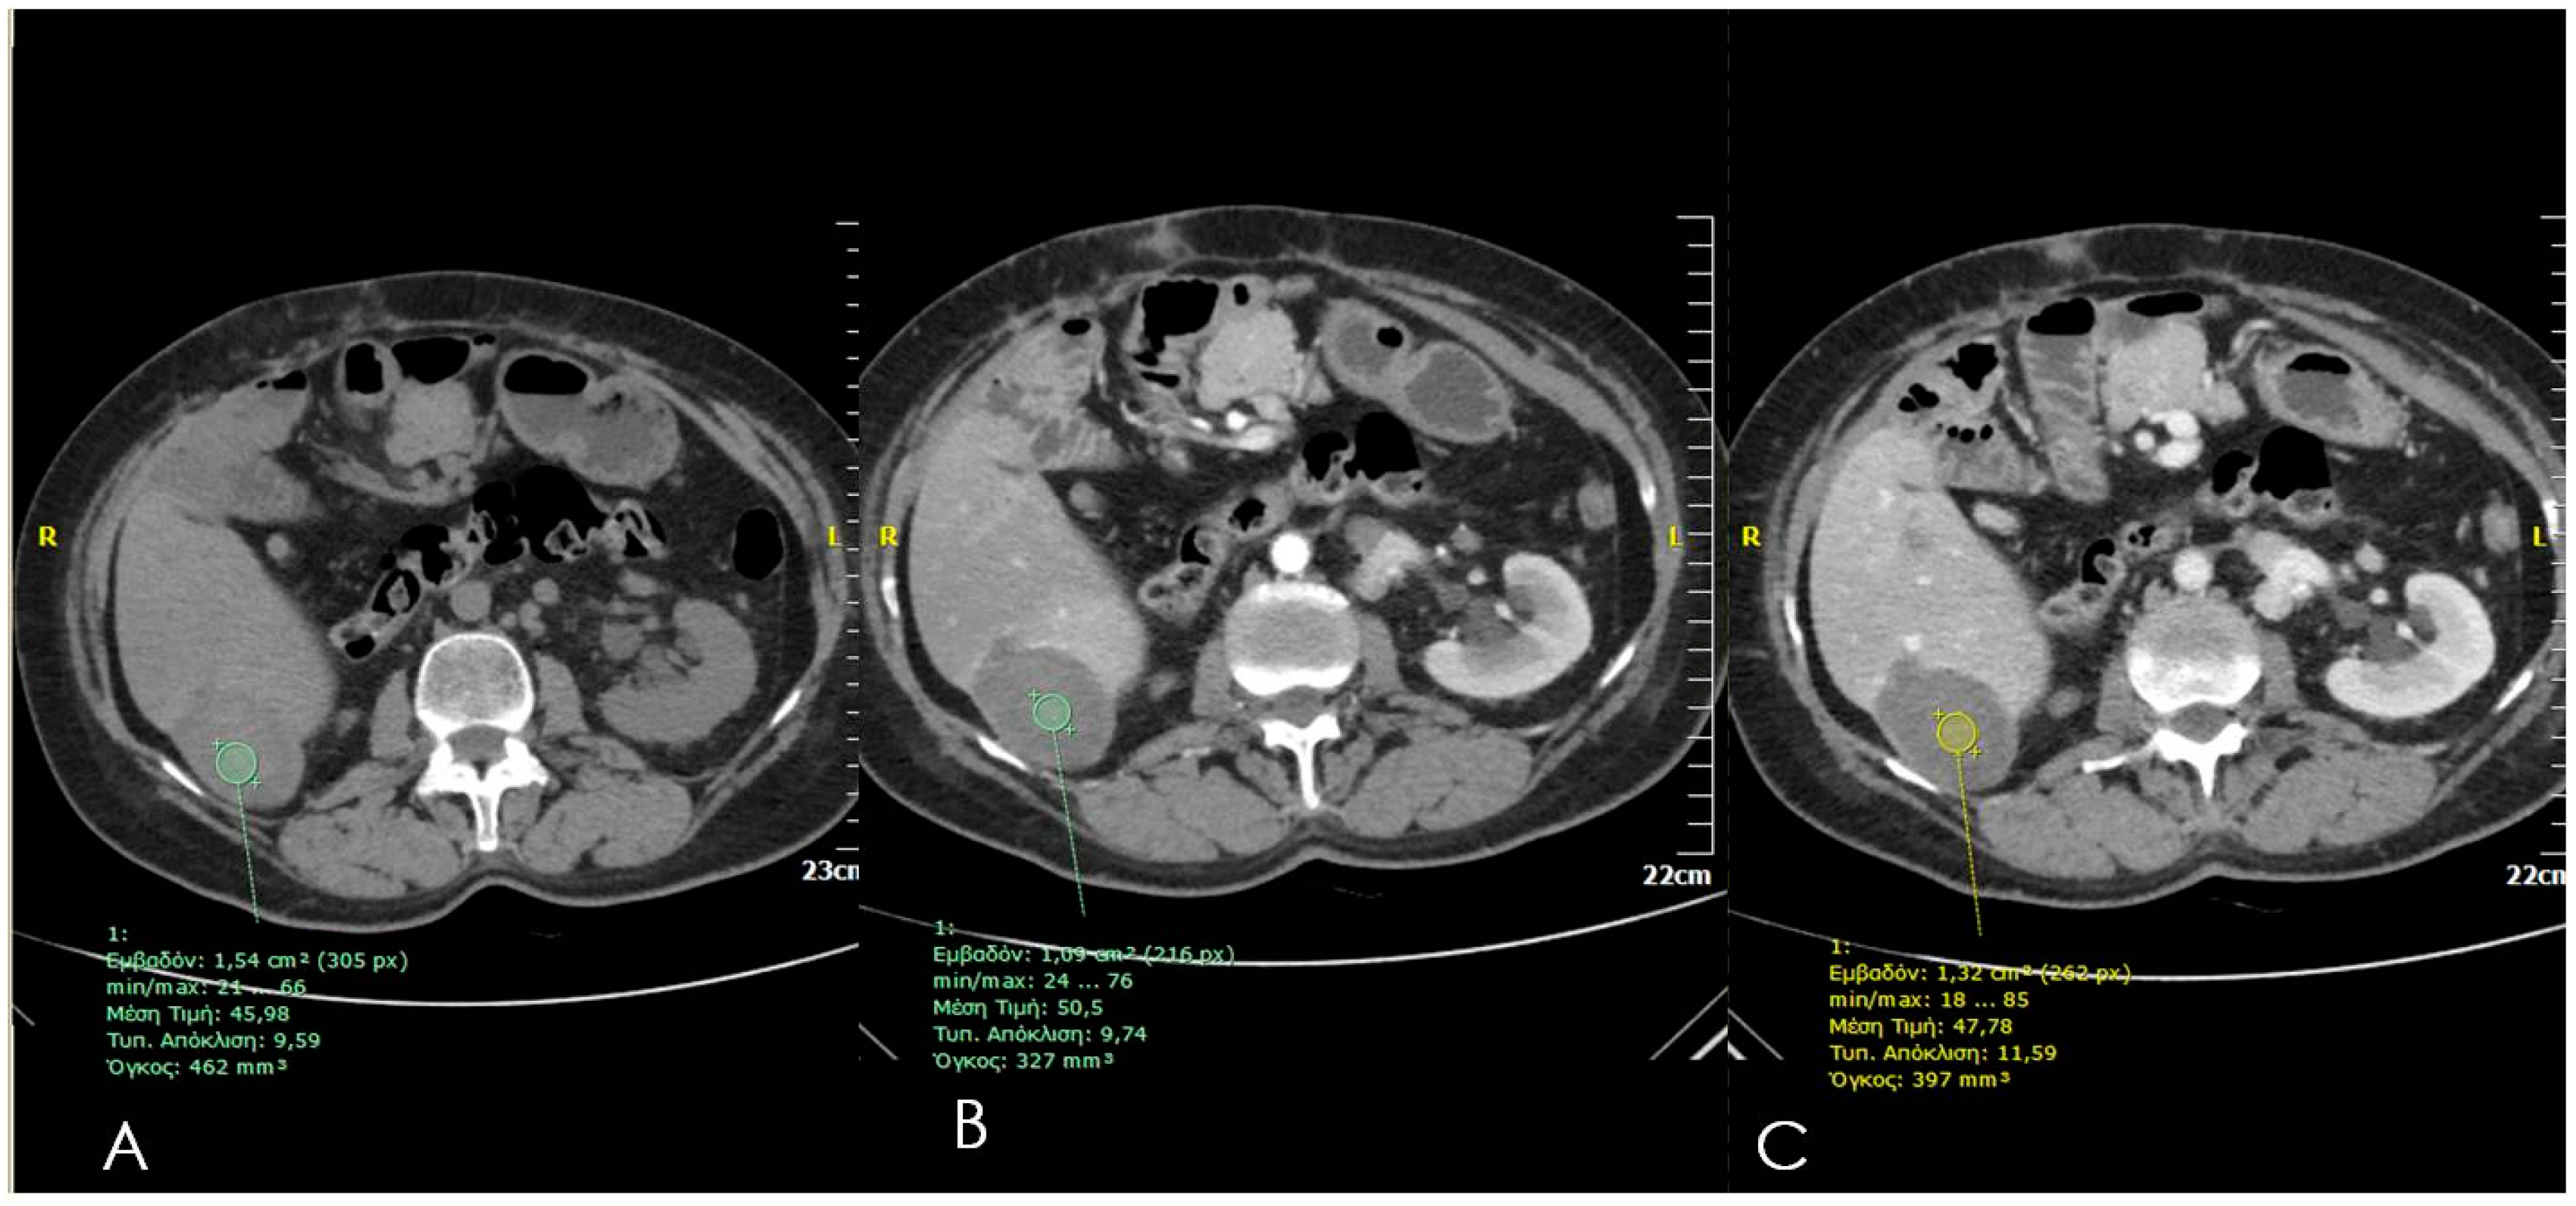

3. Ultrasounds

4. Computed Tomography (CT)